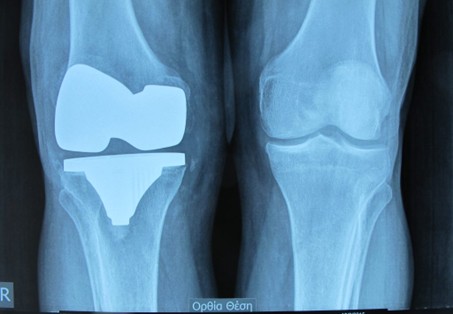

Φωτογραφία 2η : Ολική αρθροπλαστική γόνατος

Φωτογραφία 3η: Ακτινογραφία γόνατος με ολική αρθροπλαστική γόνατος